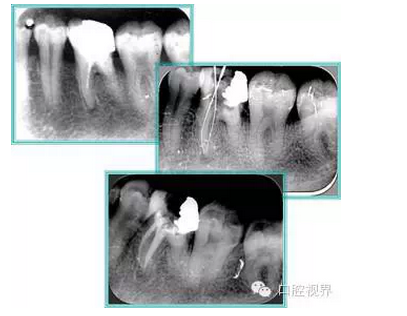

右圖及下圖為器械折斷的 X 線片。箭頭處示折斷器械。

右圖箭頭處示臺(tái)階形成。